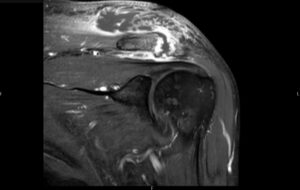

Septic Arthritis of AC Joint. MRI Coronal. Unannotated. JETem 2024